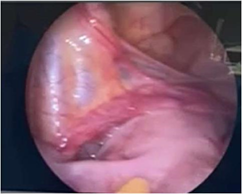

In our patient, exploratory laparoscopy was performed, which confirmed the presence of dysgenetic gonads. It was removed and histologically studied, which reported the presence of uterine tubes with fimbriae, without significant histological alterations. In both gonads, no tissue macroscopically compatible with the ovary was observed; microscopically, remains of ovarian parenchyma were observed, composed only of stroma and rete ovarii, without follicular structures or findings of malignancy (Figures 13).1–4

Figure 2 Left side.